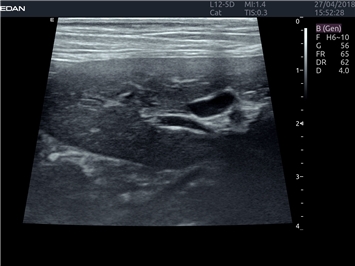

EDAN Acclarix LX4 VET представляет собой профессиональную ультразвуковую систему, специально разработанную для ветеринарных исследований. Сочетание стабильности, высокой производительности и эффективности делает эту систему идеальным выбором для современной ветеринарной практики.

• Оптимизация изображения для различных видов животных

• Улучшенная детализация структур

• Мультилучевое сложно-составное сканирование (SCI):

• Повышенная четкость изображения

• Улучшенная визуализация сложных анатомических структур

• Универсальные датчики для различных видов животных

• Специализированные предустановки для ветеринарных исследований